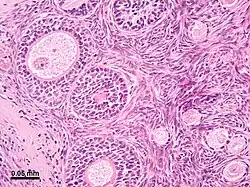

Microanatomy

The surface of the ovaries is covered with a membrane consisting of a lining of simple cuboidal-to-columnar shaped mesothelium,[7] called the germinal epithelium.

The outer layer is the ovarian cortex, consisting of ovarian follicles and stroma in between them. Included in the follicles are the cumulus oophorus, membrana granulosa (and the granulosa cells inside it), corona radiata, zona pellucida, and primary oocyte. Theca of follicle, antrum and liquor folliculi are also contained in the follicle. Also in the cortex is the corpus luteum derived from the follicles. The innermost layer is the ovarian medulla.[8] It can be hard to distinguish between the cortex and medulla, but follicles are usually not found in the medulla.

Follicular cells are flat epithelial cells that originate from surface epithelium covering the ovary. They are surrounded by granulosa cells that have changed from flat to cuboidal and proliferated to produce a stratified epithelium.